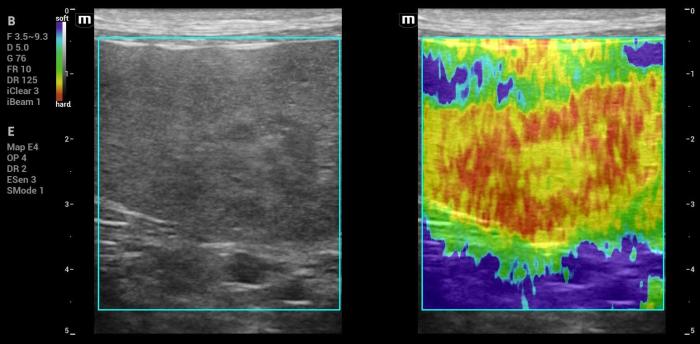

Hallazgos elastográficos (Natural Touch Elastography®): la lesión de mayor tamaño mostró rigidez elevada, significativamente superior al parénquima esplénico normal (Figura21-22).

Este comportamiento coincide con el patrón elastográfico típico de lesiones malignas descrito en la literatura5, donde los tumores esplénicos (incluyendo hemangiosarcoma) tienden a presentar velocidades de onda de corte superiores a las de lesiones benignas.

Las mediciones fueron técnicamente consistentes, sin artefactos respiratorios ni subcapsulares.

Interpretación: la combinación de esplenomegalia severa, masa sólida de ecogenicidad mixta, vascularización positiva y rigidez marcadamente aumentada en la elastografía constituye un patrón fuertemente sugestivo de malignidad. Este conjunto de hallazgos es coherente con lo reportado para tumores esplénicos de origen mesenquimal, incluida su variante más frecuente en el perro: el hemangiosarcoma.

En este caso, el comportamiento elastográfico aportó un elemento adicional de sospecha (la rigidez aumentada) que coincide con el diagnóstico definitivo y que ha sido descrito como un indicador útil en la estratificación inicial de masas esplénicas5. La presencia de dos lesiones focales dentro de un bazo con esplenomegalia avanzada es un hallazgo compatible con procesos malignos multifocales, y su comportamiento elastográfico divergente (una lesión rígida y otra de baja dureza relativa) refleja la heterogeneidad interna característica de procesos neoplásicos complejos.